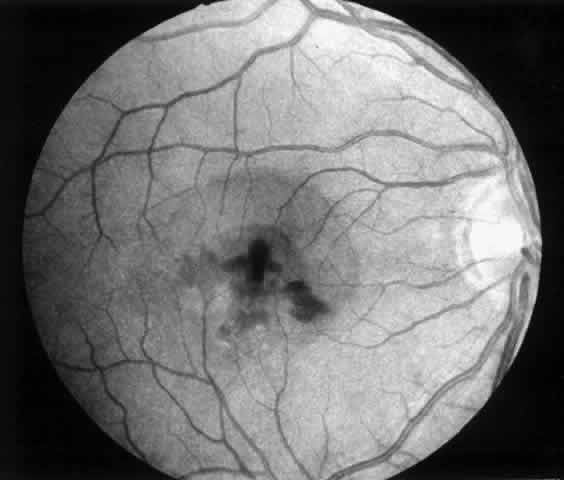

4. A 71-year-old patient with ARMD developed a recurrent choroidal neovascular membrane extending into the fovea with a preoperative vision of 20/320 (6/96) (Fig. 13). He had only marginal visual improvement after surgery (20/200 [6/60]) owing to a subfoveal RPE defect, but the size of the scotoma decreased after resolution of subretinal fluid (Fig. 14).

Fig. 13. Preoperative fluorescein angiogram (A) and Amsler grid (B) of a 71-year-old patient with age-related macular degeneration (case 4).

Fig. 14. Postoperative fundus photograph (A) and Amsler grid (B) (case 4). Central retinal pigment epithelial defect accounts for minimal visual improvement. Significant improvement is noted on Amsler grid.